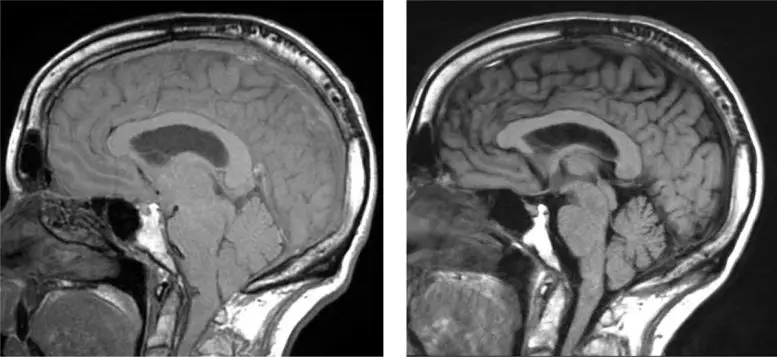

左图:大脑下垂的图像。在右边。大脑下垂的术后解决。资料来源:雪松-西奈医学中心

脑脊液(CSF)在大脑和脊髓内和周围循环,以帮助缓冲它们的伤害。当这种液体泄漏到体内时,大脑会下垂,导致痴呆症状。Schievink说,许多大脑下垂的病人可以通过核磁共振成像检测出来,如果没有被诊断出来,他建议临床医生对有明显症状的病人进行第二次检查。